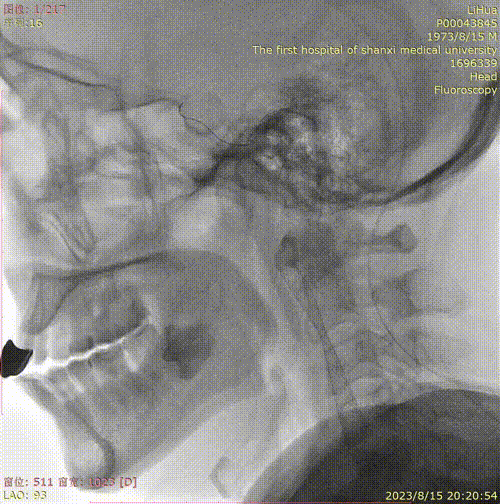

辅助检查(DSA)

主动脉弓+L-CA

波科支架怎么样径技-弓上病例大赏|第210期·右侧颈内动脉球囊扩张术+支架植入术_https://www.jmylbn.com_新闻资讯_第11张

R-CA

波科支架怎么样径技-弓上病例大赏|第210期·右侧颈内动脉球囊扩张术+支架植入术_https://www.jmylbn.com_新闻资讯_第12张

• 病例特点:右侧颈内动脉C1段重度狭窄,致远端供血区域脑梗死,手术指征明确;

在路图指引下将Filterwire保护装小心通过狭窄段,送入右侧颈内动脉岩段释放,顺保护装置微导丝将Wallstent 9.0*40mm支架于狭窄段,准确对位后于病变处释放。

顺保护装置微导丝将LitePAC5.0*30mm球囊小心通过狭窄段,准确对位后以10atm压力扩张球囊。